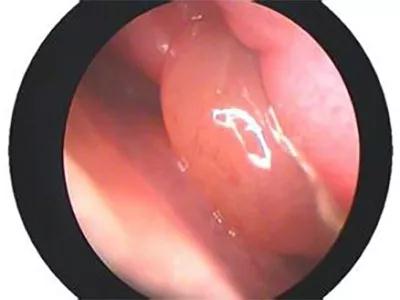

鼻息肉,顾名思义,就是在鼻腔粘膜的表面长的一个增生组织团,所以常见的表现为鼻子阻塞,和鼻内的分泌物增多,还伴有面部疼痛,产生肿胀感,还有可能导致嗅觉的减退或消失。鼻息肉是鼻部常见的疾病,大多数发生在成年人的身上。

常见的鼻息肉症状表现在持续性鼻塞,同时随着鼻息肉的长大而加重,鼻腔内分泌物增加,还经常会答喷嚏,严重的还会引发鼻窦感染,发炎化脓。鼻塞严重的患者说话时也会带着鼻音,睡觉时还容易打呼。鼻息肉很大的时候,打呼的时候还能感觉到鼻腔内有东西随着呼吸移动。

有时体积很大,甚至达数厘米大小充塞鼻腔而造成鼻塞、呼吸不通畅,或呈活瓣样启闭。